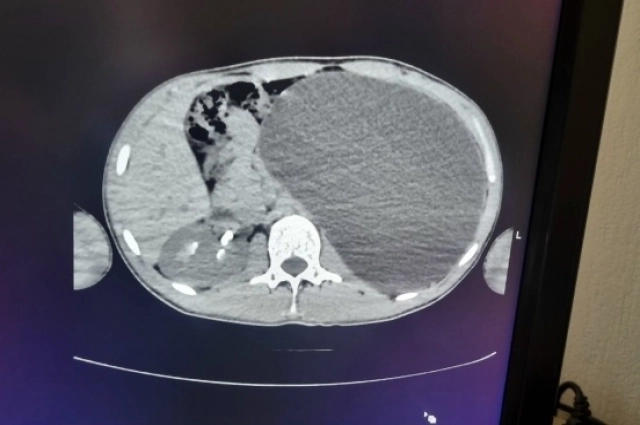

О болезни Михаил (имя изменено) узнал совершенно случайно. Он не испытывал никаких неприятных симптомов или недомогания, просто жил, планировал устроиться на работу, и для этого записался на профосмотр. Но приступить к трудовой деятельности не получилось. Сразу после УЗИ парня направили в стационар детской городской клинической больницы № 1. Снимок показал: левая почка настолько огромная, что её невозможно измерить специальным прибором.

Мальчик попал к детскому хирургу-урологу Ирине Живолуп. Медик быстро выявила гидронефроз. Это заболевание, при котором расширяется полостная система почки из-за нарушения оттока мочи. Что в свою очередь приводит к увеличению размеров почки, снижению её функции и риску развития серьёзных осложнений.

К сожалению, болезнь может долгое время протекать бессимптомно, как это и было у этого пациента. Но на профосмотре быстро нашли подозрительную аномалию. Юноше сразу провели операцию по удалению воспалённой почки, пока эта патология не привела к тяжёлым последствиям. Через небольшие проколы орган и скопившуюся жидкость вывели из брюшной полости.